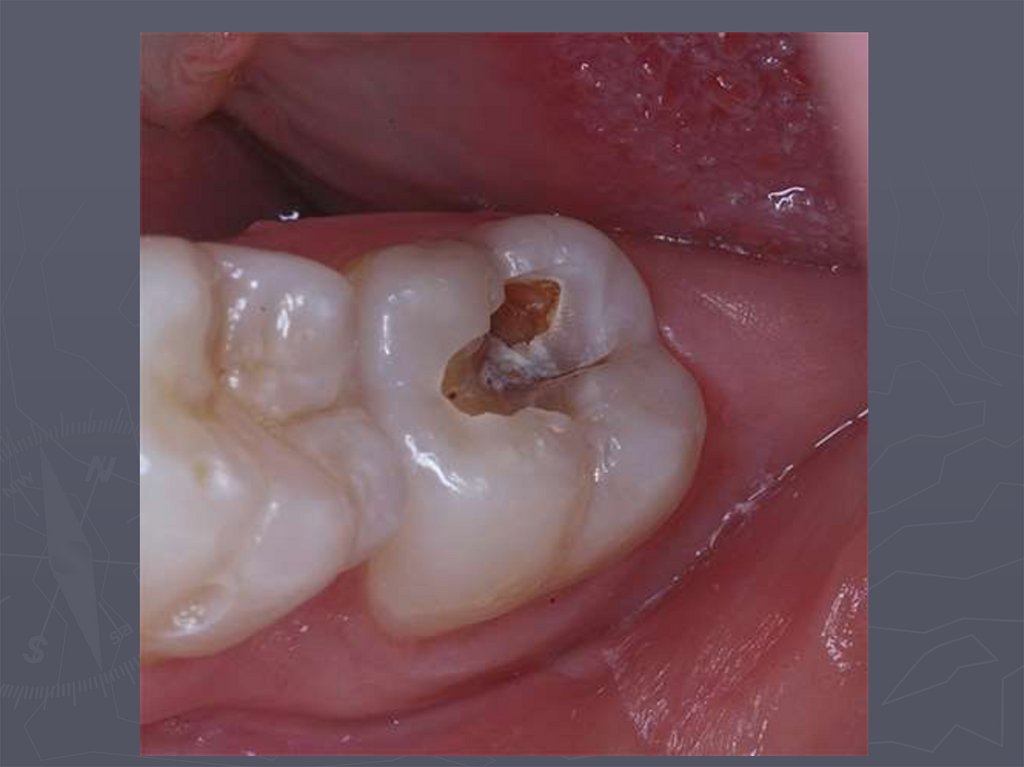

49. Глубокий кариес

► во временных и постоянных зубах с

несформированными корнями практически не

диагностируется.

Клинически глубокий кариес:

► наблюдается в постоянных зубах со сформированными

корнями;

► боли от механических ,химических, температурных

раздражителей;

► после устранения причины боль исчезает;

► кариозная полость значительных размеров;

► дентин размягченный, пигментированный;

► зондирование болезненно по дну.